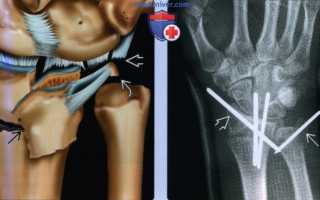

(Справа) На боковой рентгенограмме у этого пациента определяется тыльное угловое отклонение дистального эпиметафиза лучевой кости более 20°. Обратите внимание на ладонный вывих головки локтевой кости. Восстановление анатомического положения дистального эпиметафиза лучевой кости важно для восстановления целостности дистального лучелоктевого сустава. (Слева) На рисунке показаны повреждения, способствующие нестабильности дистального лучелоктевого сустава, включая сложные переломы дистального эпиметафиза лучевой и локтевой кости. Отломки лучевой кости вдавлены и отклонены под углом. Треугольный фиброзно-хрящевой комплекс разрывается при отрыве шиловидного отростка с фиброзно-хрящевым комплексом от локтевой кости и разрыве локтезапястных связок.

(Справа) На заднепередней рентгенограмме видно стабилизацию перелома спицами Киршнера через переломы лучевой кости в типичном месте и шиловидного отростка локтевой кости. Для иммобилизации наложена гипсовая лонгета.